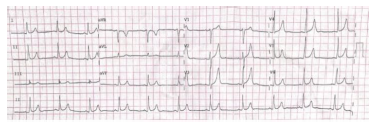

Paciente de 70 anos, sexo masculino, hipertenso e diabético de longa data e mau controle, é trazido pelo SAMU ao PS com quadro de dispneia e alteração do estado mental. Ao exame, está afebril e apresenta PA 170 x 90 mmHg, FC 98 bpm, taquidispneico, oximetria de 89% em ar ambiente. Ausculta cardíaca apresenta perda do desdobramento fisiológico da segunda bulha, sem outros achados. A ausculta pulmonar revela crepitações em ⅔ de ambos os pulmões. O paciente se encontra confuso, anictérico e apresenta flapping, além de ter tido 3 episódios de vômitos desde a admissão. Gasometria arterial: pH 7,20, pCO2 25 mmHg, HCO3 11 mEq/L, pO2 60 mmHg. Glicemia capilar 200 mg/dL. ECG conforme imagem:

Enunciado 2125919-1

Demais exames ainda em andamento. A filha do paciente, que o acompanha no momento, relata que ele foi submetido a uma cineangiocoronariografia há 3 dias, para investigar quadro de dor torácica aos esforços, mas que o cardiologista lhe disse que não foram identificadas lesões coronarianas suspeitas e, por isso, não foi realizado nenhum tratamento. Devido à alteração do estado mental, foi realizada uma fundoscopia, que revelou a presença de placas de Hollenhorst. Diante do exposto, o quadro mais provável é